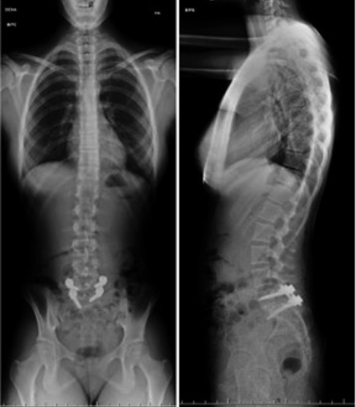

Realizamos cirugías de columna con cobertura Fonasa a través del Programa PAD, para que accedas a un tratamiento seguro, respaldado y al alcance de todos.

Las cirugías de columna hoy son más seguras y efectivas que nunca. Gracias a técnicas modernas y mínimamente invasivas, buscamos aliviar el dolor, mejorar la movilidad y permitir que retomes tus actividades cotidianas con confianza. El objetivo siempre es tu bienestar y una recuperación que te devuelva calidad de vida.